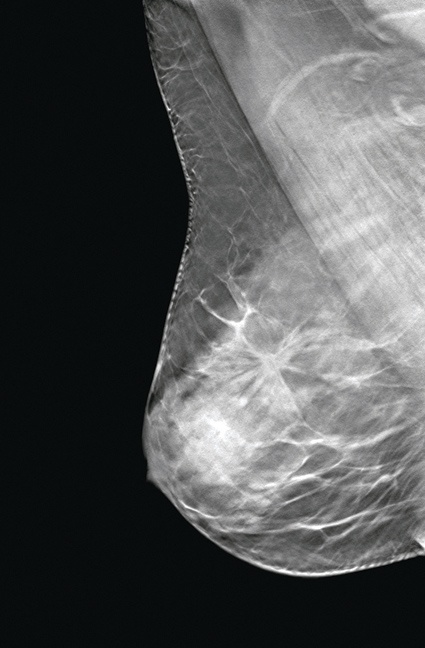

Die Entwicklungen der letzten Jahre führten zur Mammografietomosynthese ( Abb. 1), eine faszinierende Weiterentwicklung der digitalen Mammografie.

Die Röntgenröhre bewegt sich im Bogen (15 °-Winkel) während der Exposition (sehr geringe Strahlendosis) über die Brust und den Seleniumdetektor. Die Aufnahme der Brust aus verschiedenen Winkeln erlaubt eine 3-D-Rekonstruktion ähnlich einer Schnittbilduntersuchung in der CT.

Voraussetzung für die Therapie einer gutartigen oder bösartigen Veränderung in der Brustdrüse ist, dass diese klinisch oder durch die Bildgebung erst einmal gefunden wird. Die 3-D-Tomosynthese der Brust hilft Probleme, die in der 2-D-Mammografie (Summationsbild) durch sich überlagernde Gewebestrukturen entstehen, zu lösen. Überlagerungen werden durch die Erstellung von 1 mm dünnen Schichtbildern eliminiert. Dichtes Drüsenparenchym wird besser durchschaubar. Es kommt zu einer deutlicheren Erkennbarkeit von Strukturveränderungen und Dichteunterschieden im bestehenden Brustdrüsengewebe. Die 3-D-Tomosynthese schafft hier neue Möglichkeiten und erlaubt präzisere diagnostische Analysen.